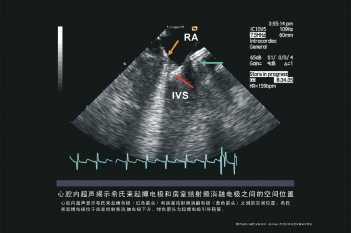

室性异位起搏点空间位置

电极空间位置